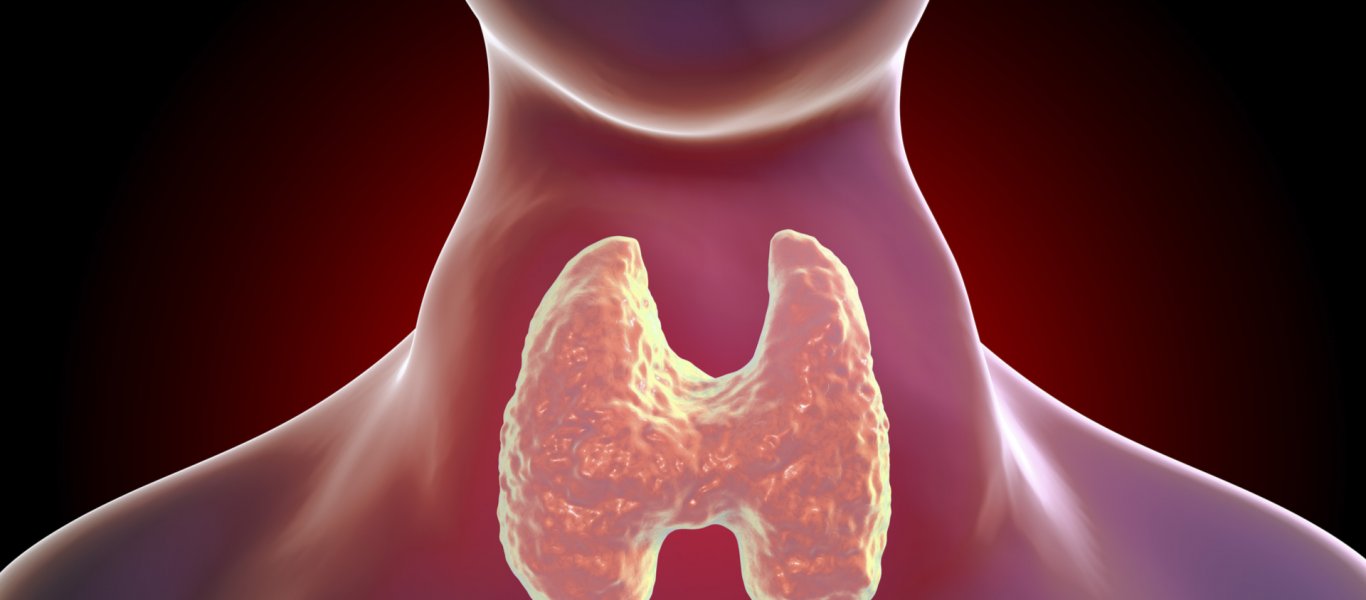

Ο υποθυρεοειδισμός είναι μια κοινή διαταραχή του θυρεοειδούς αδένα και είναι πιο διαδεδομένη στις γυναίκες.

Ο υποθυρεοειδισμός αναφέρεται στην μείωση της λειτουργίας του θυρεοειδούς αδένα με αποτέλεσμα την παραγωγή χαμηλών επιπέδων θυρεοειδικών ορμονών στο σώμα.